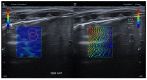

Lung ultrasound (LUS) is, at present, a standard technique for the diagnosis of acute lower respiratory tract infections (ALRTI) and other lung pathologies. Its protocolised use has replaced chest radiography and has led to a drastic reduction in radiation exposure in children. Despite its undeniable usefulness, there are situations in which certain quantitative measurements could provide additional data to differentiate the etiology of some pulmonary processes and thus adapt the treatment. Our research group hypothesises that several lung processes such pneumonia may lead to altered lung tissue stiffness, which could be quantified with new diagnostic tests such as lung sono-elastography (SE). An exhaustive review of the literature has been carried out, concluding that the role of SE for the study of pulmonary processes is currently scarce and poorly studied, particularly in pediatrics. The aim of this review is to provide an overview of the technical aspects of SE and to explore its potential usefulness as a non-invasive diagnostic technique for ALRTI in children by implementing an institutional image acquisition protocol.